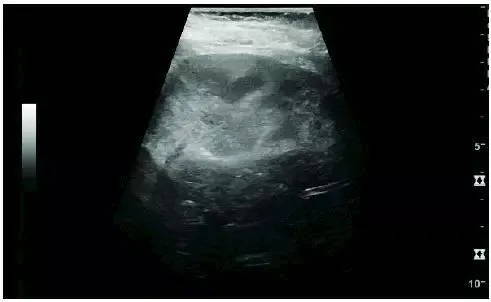

Acute Kidney Injury

Ultrasound is the method of choice for the detection of acute renal lesions; CT and magnetic resonance imaging (MRI) are options for evaluation when ultrasonography is difficult to detect. When evaluating acute renal lesions, renal echo, renal imaging, renal vascularity, renal size, and focal lesions should be observed.

Acute pyelonephritis: cortical echogenicity, ill-defined superior renal pole

Postoperative renal failure: increased cortical echo and enlarged kidneys. Kidney biopsy revealed acute tubular necrosis.